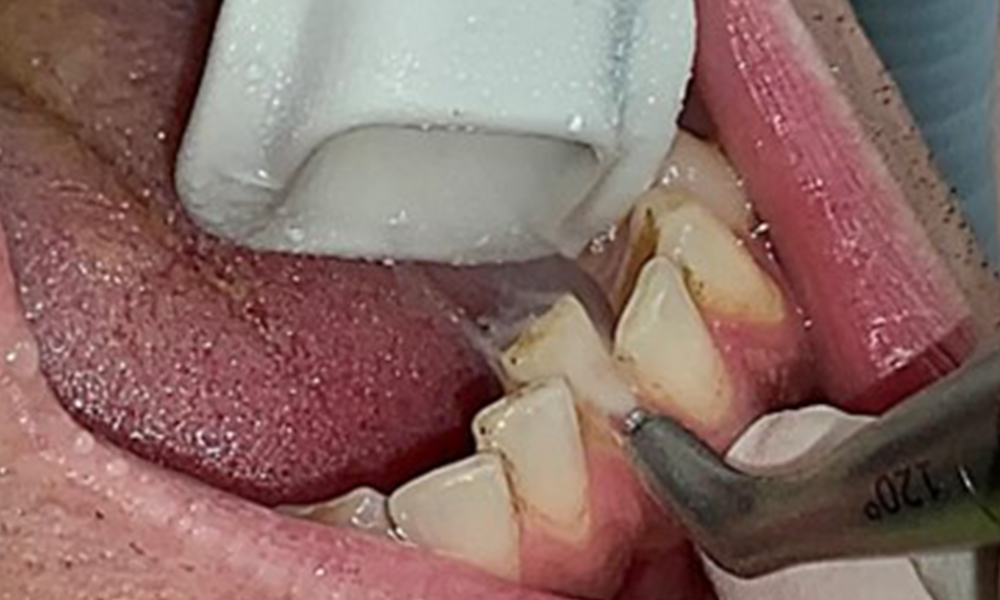

Obiectivul planului trebuie sp fie controlul riscului de boală, prin îndepărtarea biofilmului sub- și supragingival. Instrumentarul va fi ales în funcție de particularitățile pacientului. În primul rând, tartrul și eventualele concrețiuni vor fi înlăturate cu ajutorul pieselor cu ultrasunete și/sau manuale (Fig. 10).